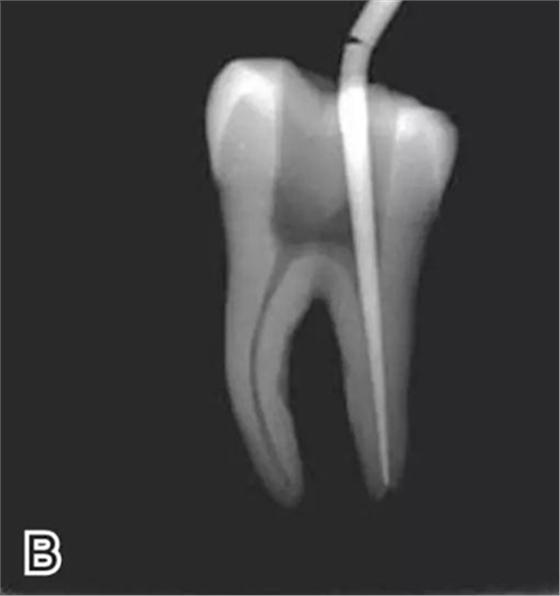

1、選擇攜熱器工作尖

根據(jù)預(yù)備后根管的粗細(xì)選擇相應(yīng)型號(hào)的攜熱器工作尖。

要求工作尖能自由到達(dá)距根尖4~5 mm(有學(xué)者提出3~4 mm)的位置并能輕微接觸根管壁,用橡皮片做好標(biāo)記(圖1)。

圖1 選擇攜熱器工作尖,A.試攜熱器尖 B.工作尖在根內(nèi)的位置